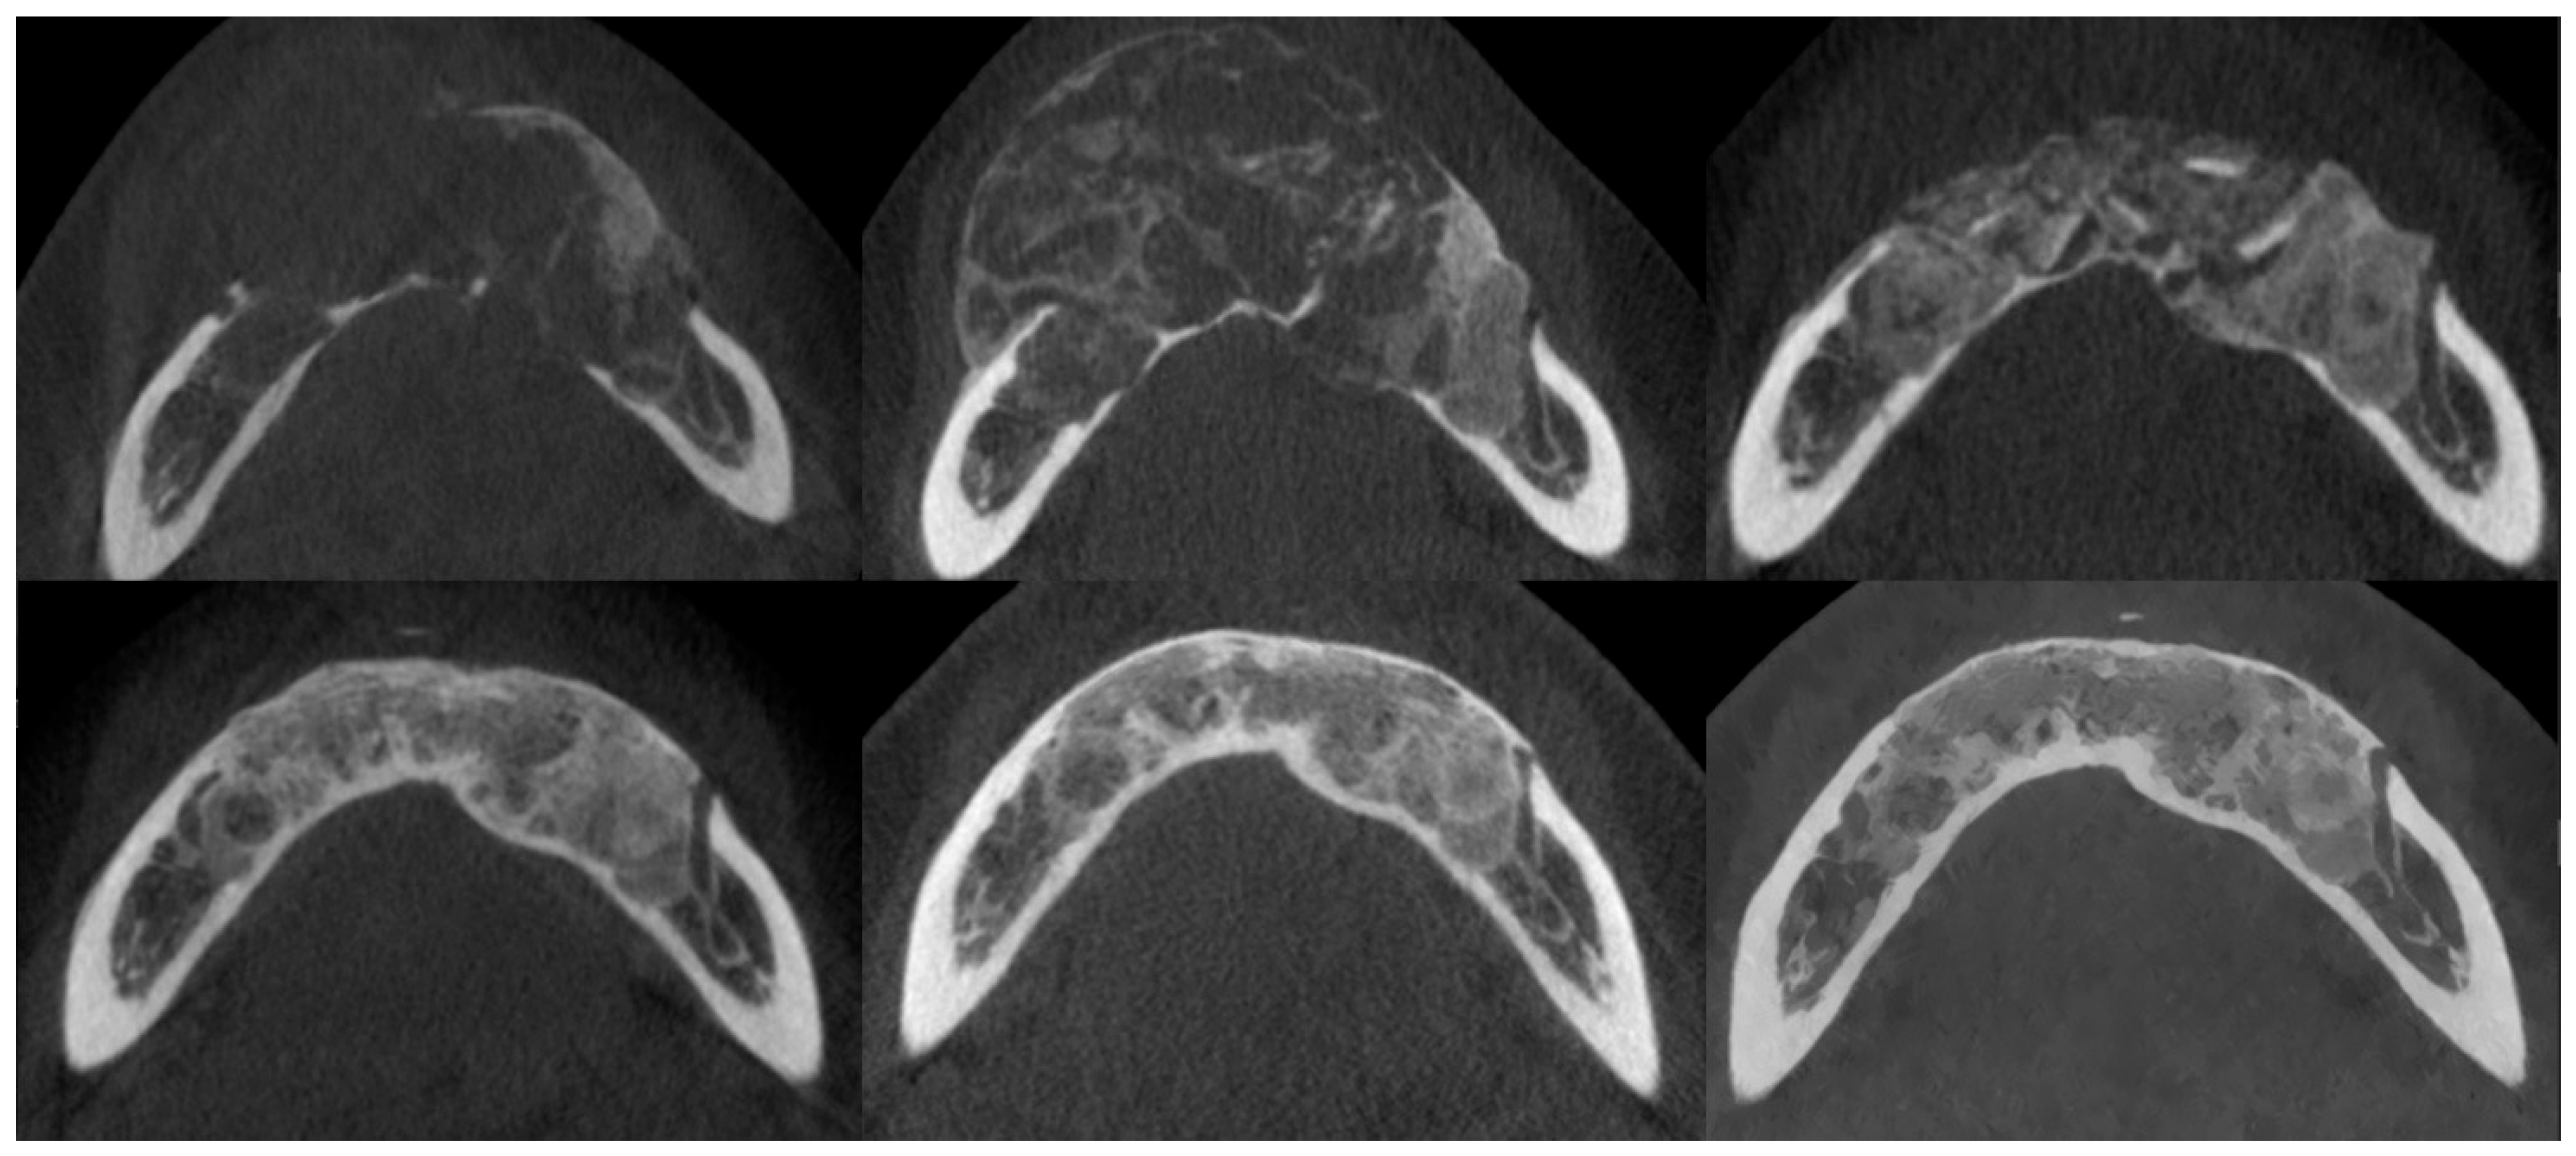

3.3. Osteosclerotic Rim (Peripheral Corticalization)

3.4. Complications During Treatment

3.5. Recurrence